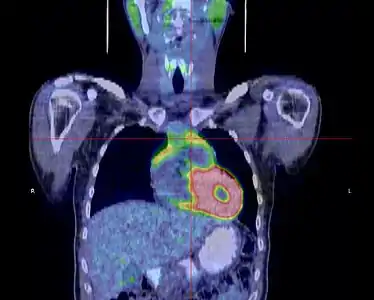

La place du TEP scanner dans le diagnostic des thymomes est encore débattue[31]. S'il existe bien une hyperfixation de la tumeur, son rôle dans le diagnostic de l'extension locorégionale reste à préciser[33].

- Thymome de type B1 en TEP scanner

Coupe frontale ; la tumeur est à l'intersection des lignes rouges.